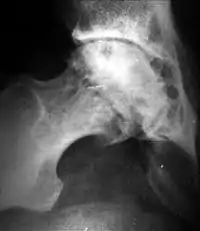

Исход артроза — полное разрушение сустава с формированием анкилоза — полной неподвижности сустава или неоартроза с неестественной подвижностью. Это сопровождается тяжёлым нарушением функции конечности. В последнее время, не дожидаясь исхода заболевания, все чаще применяют специальные операции по замене сустава протезом — эндопротезирование сустава. На рисунке изображена типичная для терминальной стадии артроза коленного сустава варусная деформация колена в сочетании с боковой патологической нестабильностью коленного сустава. Артроз блоковидного или шаровидного сустава, такого как тазобедренный, завершается анкилозированием. При этом замыкание сустава обычно происходит в нефизиологическом (порочном) положении конечности. В данном случае мы видим бедро в положении сгибания и приведения, при котором нога укорачивается, а ось конечности и биомеханика опорно-двигательной системы существенно нарушается.

При остеоартрозе утрачивается амортизационная функция суставных хрящей, предохраняющих костную ткань от механических перегрузок. Как компенсация развивается остеосклероз субхондральной губчатой кости. Особенно он выражен при коксартрозе в крыше вертлужной впадины, распространяясь иногда почти на все тело подвздошной кости. Однако рано или поздно этот механизм компенсации становится недостаточным. Механические силы, передающиеся непосредственно с одной суставной поверхности на другую, вызывают атрофию от давления их наиболее нагружаемых участков и прежде всего центральных отделов суставных головок. Вследствие этого они уплощаются и одновременно расширяются.

Результатом поражения суставных хрящей являются очаговые дистрофические и некротические процессы в субхондральной губчатой кости, соответствующие локальным пикам механических напряжений. В результате этих процессов формируются кистовидные образования. Последние наиболее характерны для коксартроза, при котором они часто множественны и достигают больших размеров. положение (эрозивный артроз).

Рентгенологическое исследование играет важную роль в распознавании этиологических факторов при вторичных остеоартритах. Так, при посттравматических остеоартрозе оно даёт возможность обнаружить костные деформации после внутрисуставных переломов, установить характерные признаки диспластических артрозов, особенно в тазобедренном суставе, на рентгенограммах можно выявить краевые дефекты суставных поверхностей, остеопороз и атрофию костей при постартритических артрозах. С помощью рентгенографии можно установить связь между отдалёнными от суставов деформациями костей диспластической, посттравматической или иной природы. Например, угловое искривление оси длинной трубчатой кости, сопровождающимися изменениями условий нагрузки на суставы, и вторичным (статическим) остеоартрозом. Рентгенологическое исследование даёт возможность выявить такие причины артроза, как внутрисуставное тело при хондроматозе сустава[19].